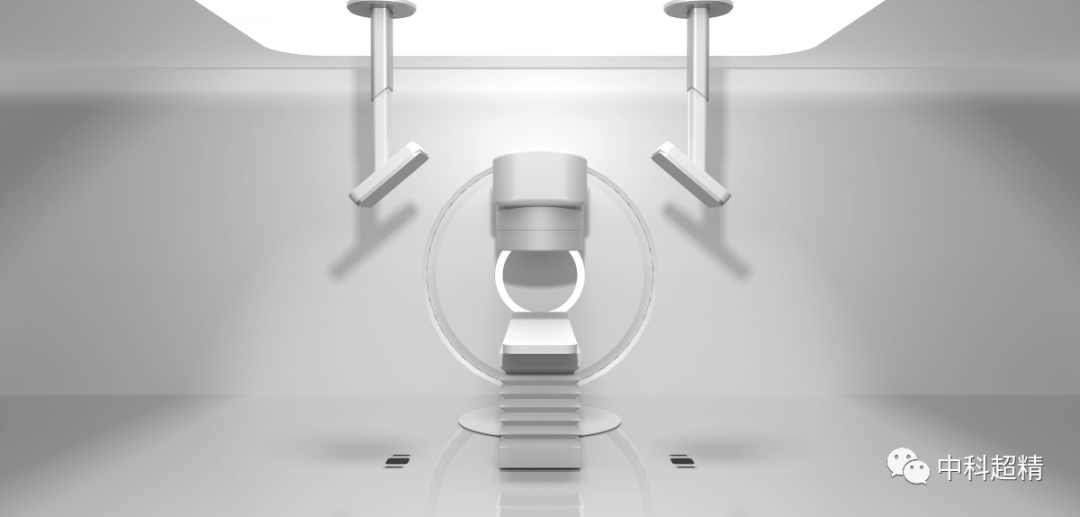

“麒麟刀·木” X射線圖像引導系統

(KylinRay-XGPS)

KylinRay-XGPS是面向腫瘤放射治療的圖像引導系統,主要基于透視成像對腫瘤患者放射治療過程實施精確定位,是中科超精在精準照射領域布局的另一重磅產品。該系統采用KV級透視成像和圖像智能配準技術,基于放射治療計劃以及三維CT圖像生成DRR圖像與采集投影圖進行2D-3D圖像配準,精確探測出 6個自由度的擺位誤差,真正實現了對患者在每個分次的高質量圖像引導。此產品可以獨立安裝,無需與直線加速器建立電氣連接,可適應各種主流加速器型號以及不同結構的機房,并幫助廣泛的用戶以最低的成本實現圖像引導的放射治療。